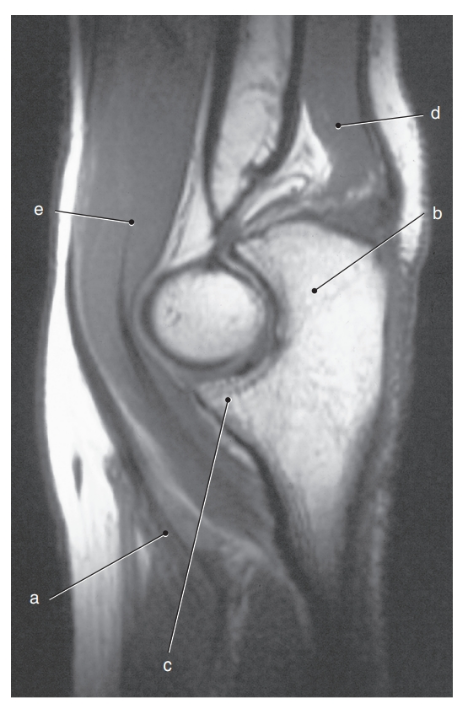

What is letter e ?

Olecranon process

What is letter a ?

Lateral epicondyle

What is letter c ?

Coronoid process

What is letter a?

Biceps brachii tendon